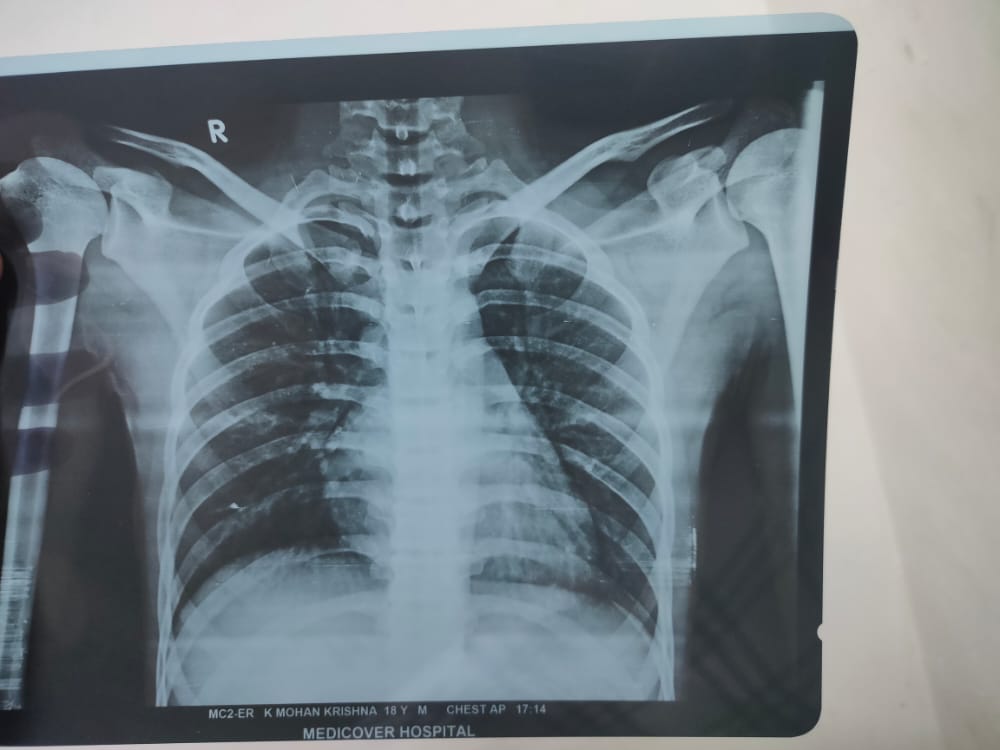

This person need help to get from spinal injury, he is a younger boy of 18 years old, he has no father, financial backwards family, his mother having hop on donors to get surgery to his son back normally. And doctors said for surgery need 6 lacks . Hoping on you get some support, who can give donations.

Here attached his details.